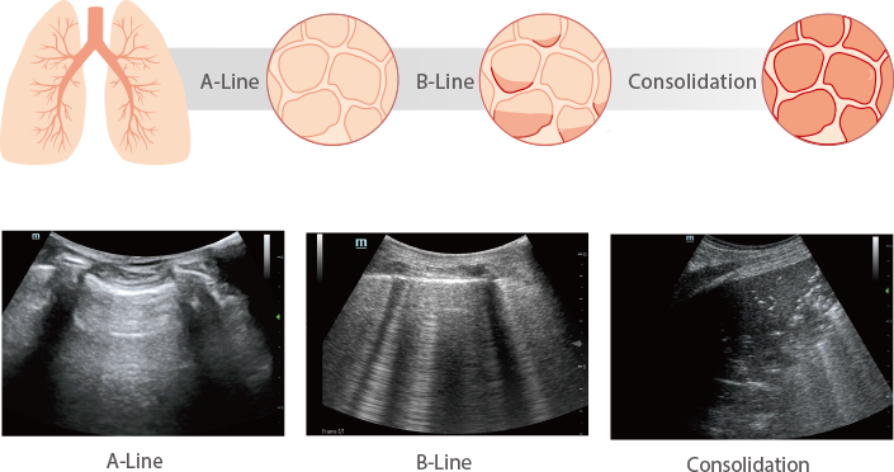

Why Lung Ultrasound?

a. Shows typical sonographic signs of COVID-19 disease

b. Higher degree of accuracy than bedside chest radiograph*

c. Gives indications for the diagnosis/triage and management of COVID-19